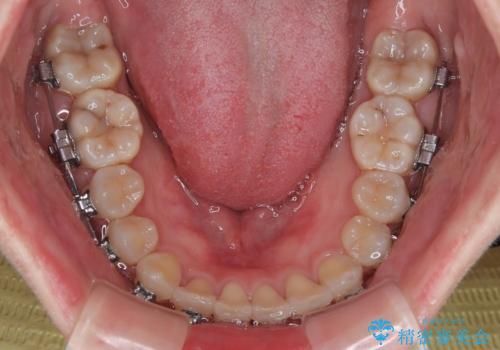

- 矯正装置

- メタルブラケット

マウスピースでもワイヤーでも対応可能でしたら、捻転が非常に強いことから、患者様と相談の上ワイヤー装置にて矯正治療を行うこととしました。

捻転を解消する際に、歯列全体が前方に突出して出っ歯の仕上がりとなることが懸念されたため、補助装置を用いて上顎歯列全体を後方に移動する力をかけることとしました。